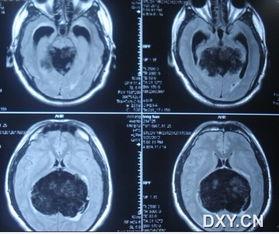

2. 影像学照片:包括X光、CT、MRI等,这些照片可以显示肿瘤的位置、大小和形态。